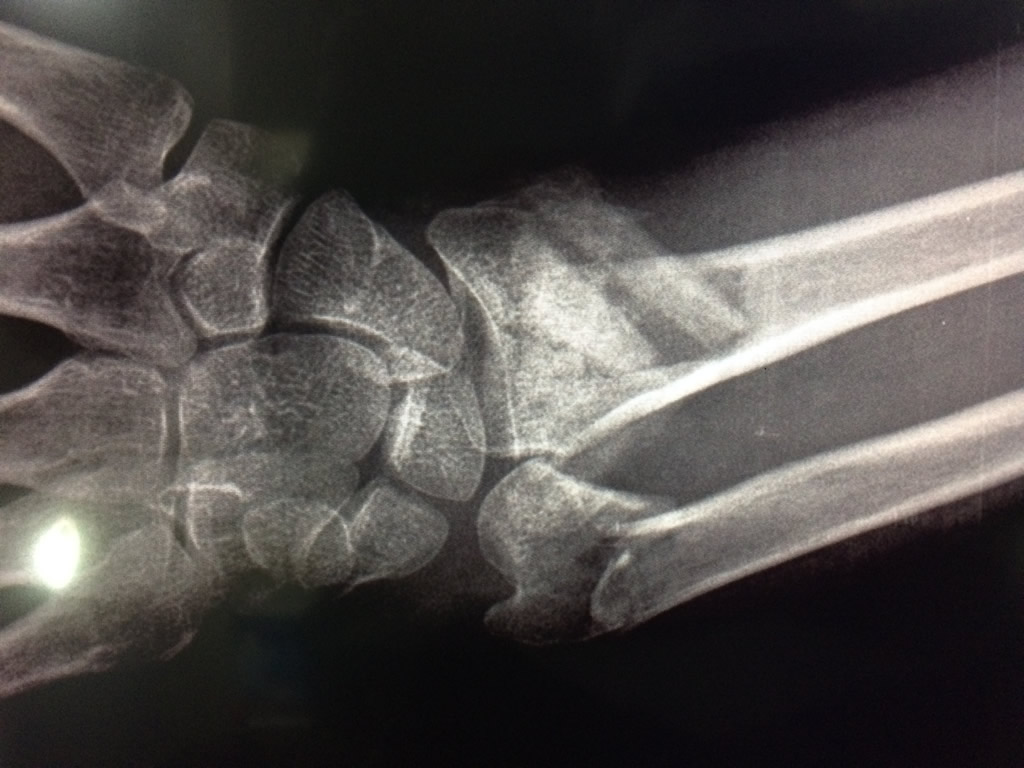

Cirugía de Muñeca y Mano

Los procedimientos más comunes en cirugía de la mano son aquellos destinados a reparar traumatismos, incluyendo lesiones de tendones, nervios, vasos sanguíneos, y articulaciones; huesos fracturados; y quemaduras, cortes, y otros daños de la piel.